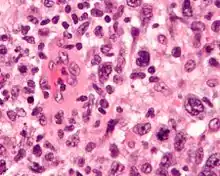

| Micrograph of an anaplastic large-cell lymphoma. H&E stain. | |